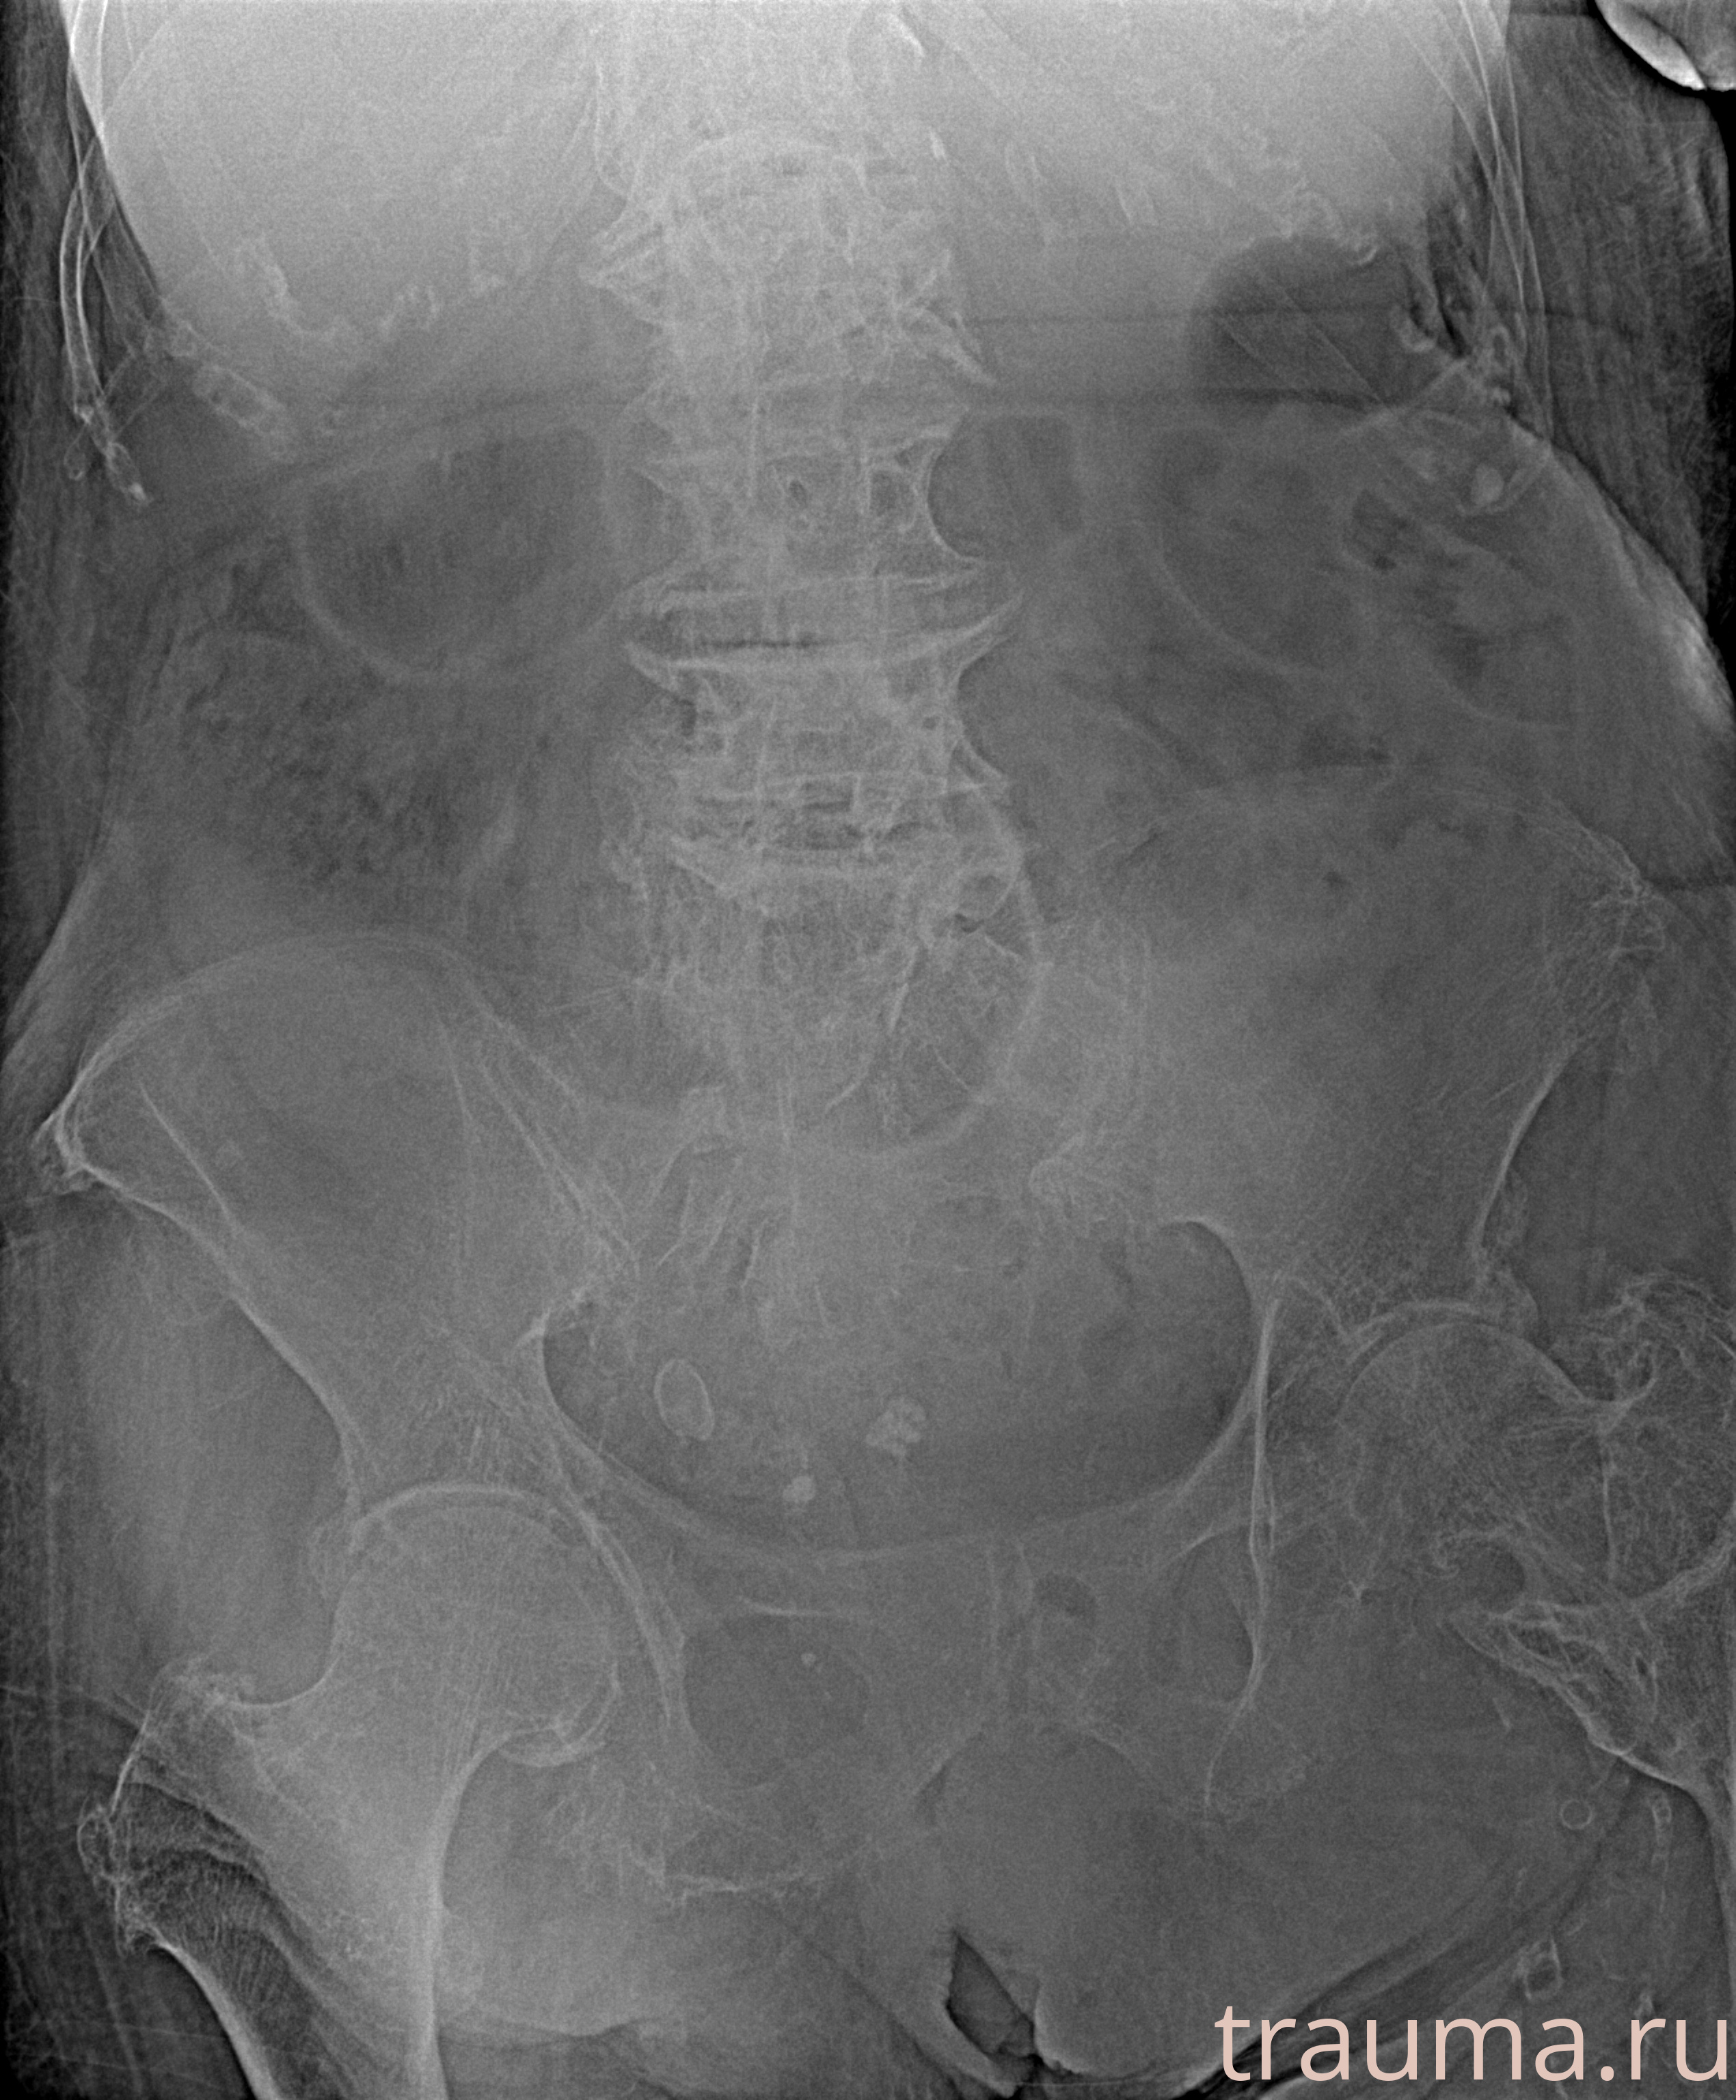

Рентген на дому: по вашему адресу приезжает врач-рентгенолог, травматолог-ортопед с мобильным рентгеновским аппаратом, проводит диагностику травмы или заболевания, делает необходимые рентгенограммы, дает рекомендации по дальнейшему лечению. Получить качественные снимки в домашних условиях возможно благодаря уникальной методике, разработанной МосРентген Центром для института  Склифосовского

при переломе шейки бедра и пневмонии от компании МосРентген Центр - партнера Института имени Склифосовского